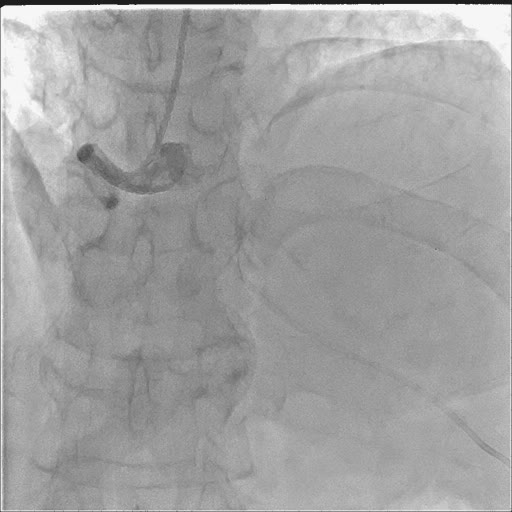

造影如下:

在透视进导丝的过程中就发现了问题--心脏游离缘出现“透亮带”!!!

抓紧时间完成造影: